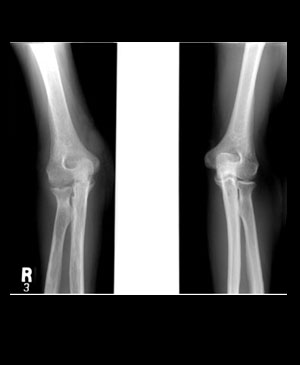

Rheumatoid arthritis

X-선상

골음영의 감약(osteoporosis) : 피질(cortex)의 불선명화, 골량의 거침

Rad bite erosion

척골(ulna)의 경상돌기(styloid process) erosion 은 중요 소견

관절강의 협소화는 손에서 균등하게 보임

섬유성 또는 골성강직 : 수근골, 족근골에 보이며 지절골에는 없다

Rheumatism결절 : , 팔꿈치등에 빈발

골막반응(periosteal reaction)이 보인다

굴곡변형(flexion deformity)